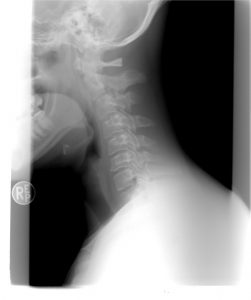

Ważne jest, aby znać tę technikę, ponieważ ból szyi jest powszechnym problemem w naszym społeczeństwie. Ćwiczenia Rolanda Brachta mogą pomóc Ci poczuć ulgę w bólu niemal natychmiast.

Należy usiąść na wygodnym krześle i trzymać plecy prosto. Następnie należy położyć ręce na głowie. Następnie, gdy ręce nadal znajdują się na głowie, należy przesunąć szyję do przodu, aby uzyskać zgięcie szyjne. Ręce powinny być luźno trzymane na głowie. Nigdy nie należy ciągnąć głowy do przodu.

Ćwiczenie może powodować lekkie pieczenie w okolicy karku. Można również odczuwać lekkie rozciąganie w odcinku szyjnym. Rozciąganie występuje również w dolnych partiach kręgosłupa.